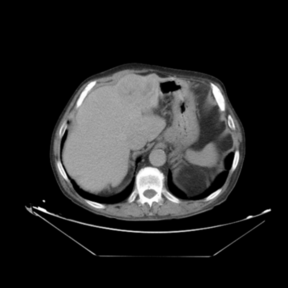

In addition to the previous measurements, the visual outcomes of two of the experiments are shown in Figures 3 and 4, whose purpose is to highlight the most illustrative differences (from a medical point of view) between the results provided by the compared methods. In Figure 3, we observe a normal size of the liver, with discretely irregular contours and homogeneous signal intensity. In hepatic segment II, there is a lesion of 40 mm of maximum axis, encapsulated and with well-defined contours and heterogeneous enhancement in arterial phase (after administration of intravenous contrast), suggestive of hepatocellular carcinoma (HCC). In this slice of the CT scan, we can also observe the aorta that shines in the arterial phase, the lower area of the stomach and the upper area of the spleen. In Figure 4, the liver has a normal size with discretely irregular contours in relation to changes due to chronic liver disease. In hepatic segment IV, a 36 mm diameter focal lesion is identified, which has arterial phase enhancement with a small area of necrosis of 13 mm; it corresponds to a HCC previously chemoembolized with partial necrosis. In this slice of CT, we can also observe the aorta, the gastric chamber and the spleen. When comparing the two methods under study, it can be seen how in Figure 3 the resulting registered datasets are very similar. However, looking closely, it can be noticed that in the right part of the image (left side of the patient) the shape and width of the structures corresponding to the stomach and the spleen in Figure 3(d) match better those in the reference dataset. Likewise, the part of the rib at the upper right of the image is more similar to the same region in the reference dataset by using the proposed method. Regarding the experiment shown in Figure 4, it can be easily appreciated how the geometrical matching (with respect to the reference dataset, Figure 4(a)) of the structures in the right side of the image (specially the gastric chamber) is visually more satisfactory in Figure 4(d). Moreover, the area of tumor necrosis which results from the proposed method is also slightly better aligned.

Arterial phase (reference dataset, R) Portal venous phase (template dataset, T)

(a) Arterial phase (reference dataset, Failed to parse (MathML with SVG or PNG fallback (recommended for modern browsers and accessibility tools): Invalid response ("Math extension cannot connect to Restbase.") from server "https://mathoid.scipedia.com/localhost/v1/":): {\textstyle R}

)

(b) Portal venous phase (template dataset, Failed to parse (MathML with SVG or PNG fallback (recommended for modern browsers and accessibility tools): Invalid response ("Math extension cannot connect to Restbase.") from server "https://mathoid.scipedia.com/localhost/v1/":): {\textstyle T}

Registered template, T_u (CR-based method) Registered template, T_u (proposed method)

(c) Registered template, Failed to parse (MathML with SVG or PNG fallback (recommended for modern browsers and accessibility tools): Invalid response ("Math extension cannot connect to Restbase.") from server "https://mathoid.scipedia.com/localhost/v1/":): {\textstyle T_\mathbf{u}}

(CR-based method)

(d) Registered template, Failed to parse (MathML with SVG or PNG fallback (recommended for modern browsers and accessibility tools): Invalid response ("Math extension cannot connect to Restbase.") from server "https://mathoid.scipedia.com/localhost/v1/":): {\textstyle T_\mathbf{u}}

(proposed method)

Figure 4. Visual outcomes of experiment 5 (slice 12): registration of arterial and portal venous phases of patient 2